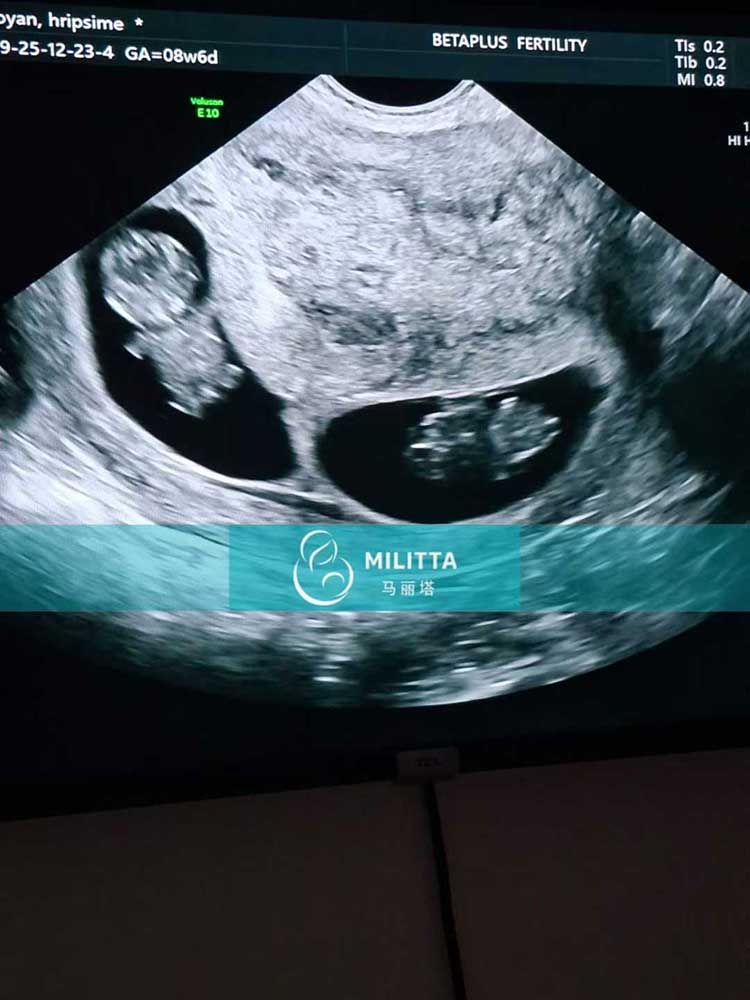

喜悦分享!为三位格鲁吉亚客户的试管妈妈完成皆处于孕9周的B超检查。令人欣喜的是,其中两位妈妈是双胎妊娠,一位是单胎,所有宝宝胎心搏动均强而有力,发育良好